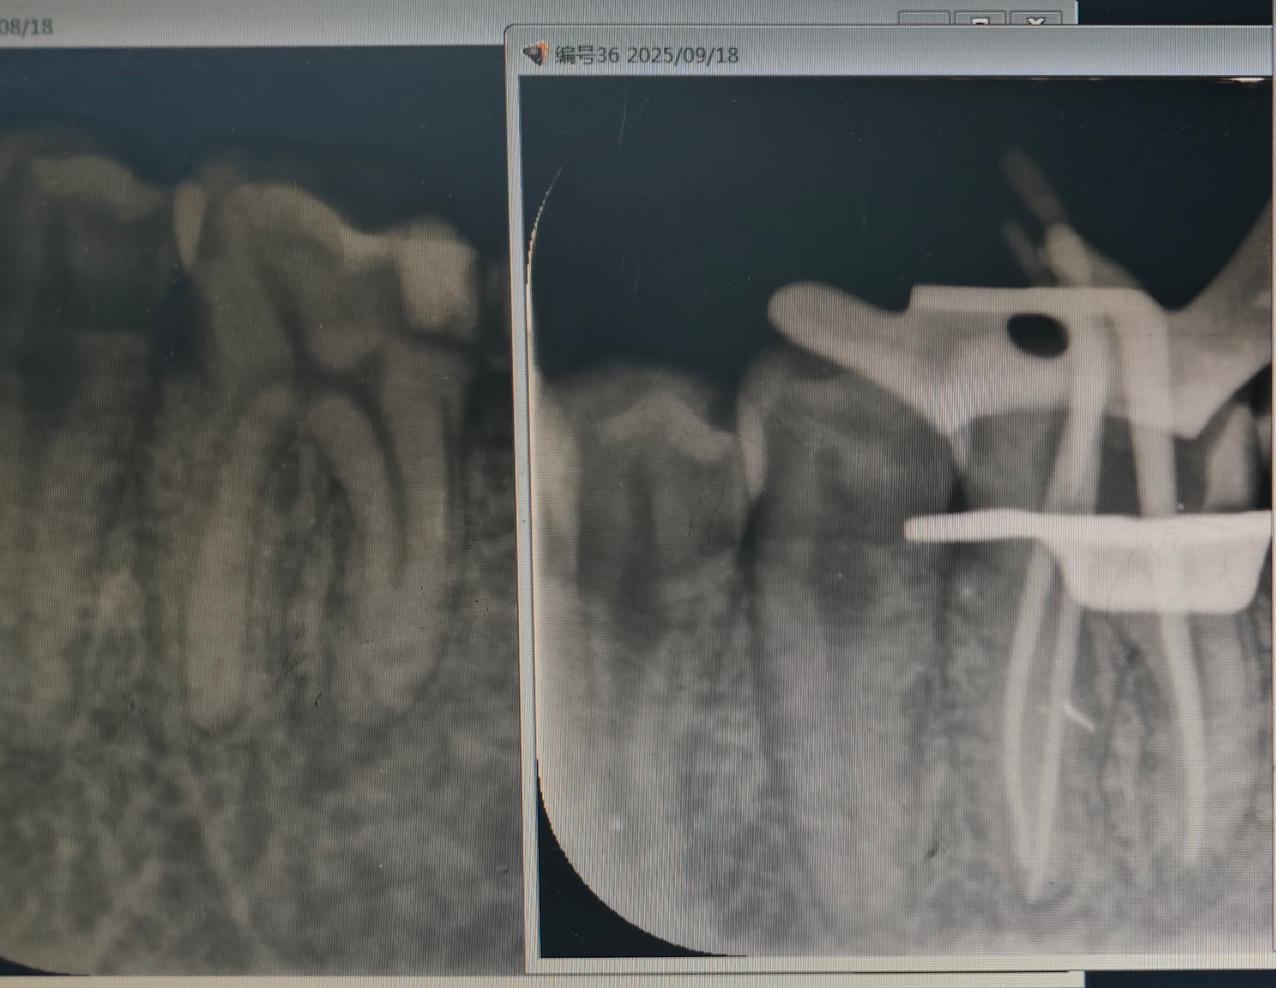

根管治疗

根管治疗 - 案例一

术前 术前

术后 术后

根管治疗 - 案例二